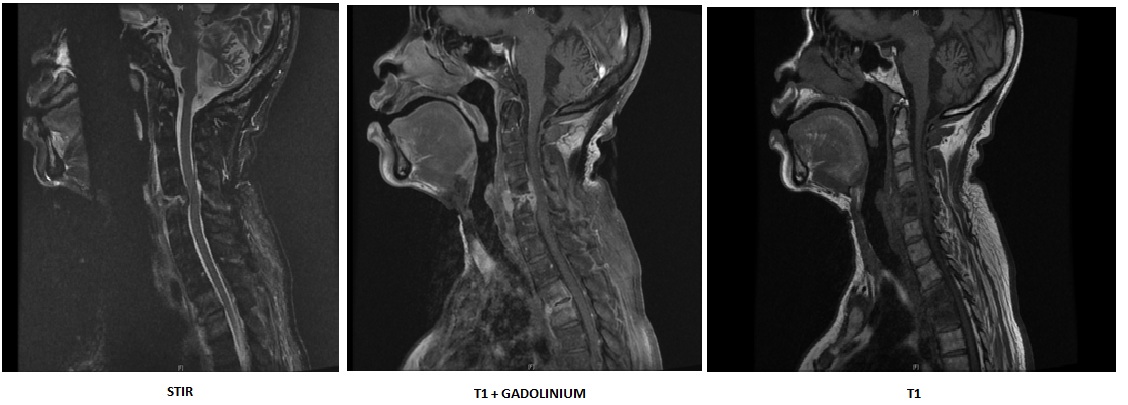

Atteinte rachidienne cervicale évoluée dans le cadre d'une spondyloarthrite axiale radiographique

Spondylodiscite multifocale du rachis cervical et du rachis dorsal